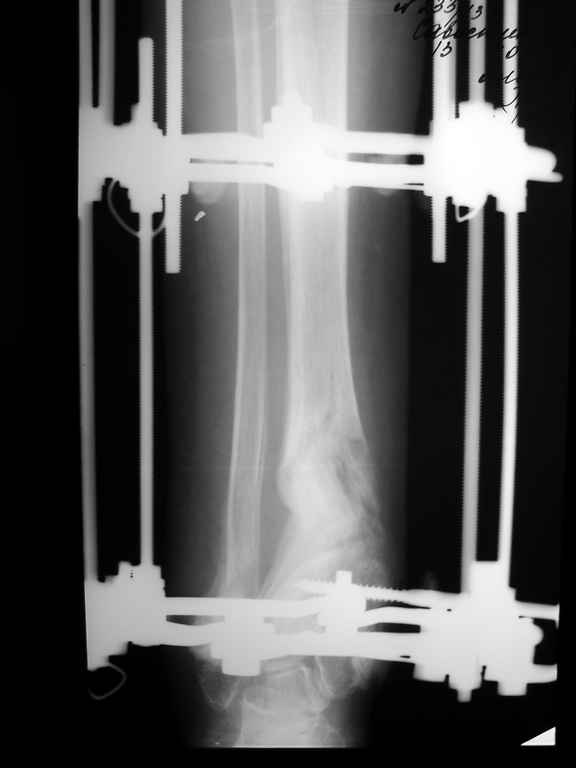

Девушка 17 лет: боли в голеностопном суставе,ограничение движений в суставе,укорочение голени,хромота Из анамнеза в раннем детском возрасте перенесла гематогенный остеомиелит дистального отдела большеберцовой кости - зона роста частично закрылась сформировалась варусная деформация голеностопного сустава + укорочение костей голени на 6 см Произведена корригирующе-удлиняющая остеотомия сначала большеберцовой,затем малоберцовой костей, устранена деформация, ликвидировано укорочение. С возрастом наросло укорочение до 3 см,клинически умеренная вальгусная деформация голеностопного сустава. Объём движений в суставе в пределах 15 град. Отмечает переодически болевой синдром, после осевой перегрузки,пользуется обувью с компенсацией, ортезом на голеностопный суставВопрос: есть ли показания для оперативного лечения: артропластика? артродез? голеностопного сустава. Какие мысли,коллеги?